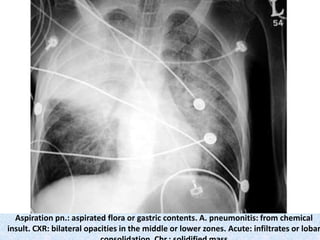

Aspiration pn.: aspirated flora or gastric contents. A. pneumonitis: from chemical

insult. CXR: bilateral opacities in the middle or lower zones. Acute: infiltrates or lobar

Aspiration pn.: aspiratedflora or gastric contents. A. pneumonitis: from chemical insult. CXR: bilateral opacities in the middle or lower zones. Acute: infiltrates or lobar

Rt. middle lobecollapse with obliteration of R heart border